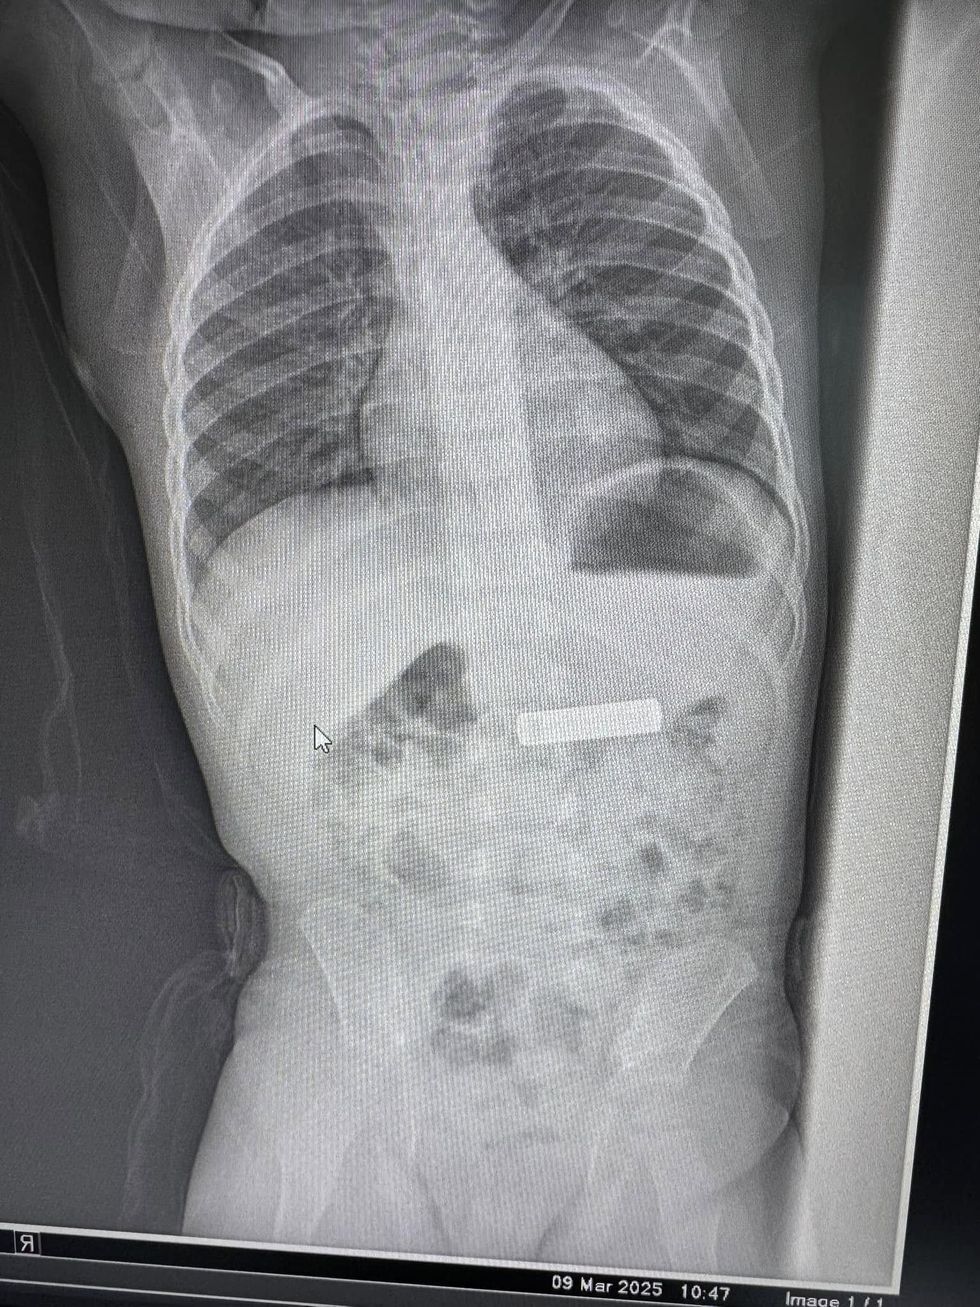

Gastroenterologu në Gjilan ia largon dyvjeçarit baterinë e telekomandës nga stomaku

Gastroenterologu Besnik Elezi ka realizuar me sukses heqjen e një baterie telekomande nga stomaku i një fëmije 2-vjeçar.

“Largohet nga stomaku bateri e telekomandës te fëmija 2 vjeç K.Sh.”, ka shkruar Elezi, duke ndarë edhe disa fotografi nga procedura.

Më poshtë mund të shihni imazhet e publikuara nga vetë mjeku.